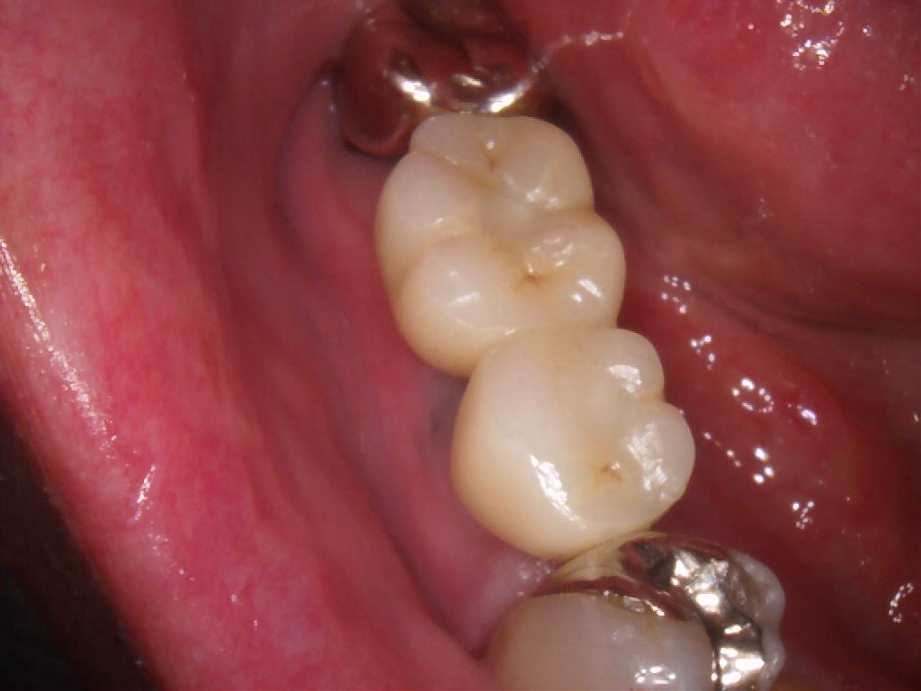

治療後

- 右下56番パーシャルデンチャー部のインプラント治療

- 60代女性 右下56番にパーシャルデンチャーを装着しており機能及び審美的に問題を抱えている。

- まず、CT撮影による精密な骨の分析・治療計画を立てガイドを使いインプラント埋入しインプラントが骨と結合するのを待つ間に仮の歯を入れます。その後本歯を作成して装着しました。

- インプラント埋入からジルコニアセットまで三か月半

※自由診療となります - ■総額:¥660,000(税込み) ■内訳:埋入(ガイド込み)¥200,000×2、仮歯¥20,000×2、被せ物¥80,000×2